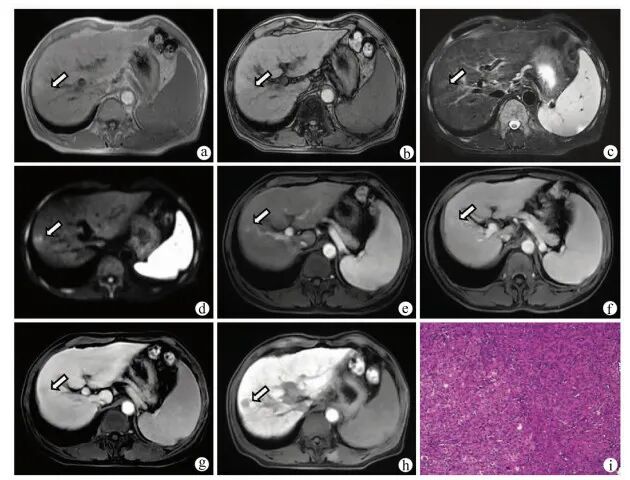

图2 患者男,46岁,HBV感染者,肝硬化合并eHCC注:a,同相位MR T1WI示肝脏S8段等或稍低信号(箭头);b,病灶反相位信号减低,提示其内存在脂肪变性(箭头);c,T2WI呈稍高信号;d,DWI呈稍高信号;e,增强扫描动脉晚期呈等信号(箭头);f、g,门静脉期及延迟期呈低信号(箭);h,肝胆期呈低信号;i,病理学诊断为高分化HCC,其内存在较多脂肪(HE染色,×100)。

3.2.1 T1WI eHCC主要呈等信号,可呈稍低信号,仅极少数表现为高信号;部分结节反相位信号减低,提示其内存在脂肪变性。

3.2.2 T2WI eHCC主要呈等或稍高信号,仅极少数表现为低或混杂信号。

3.2.3 DWI eHCC多表现为DWI高或稍高信号,ADC图呈低信号,提示病灶水分子弥散受限。

3.2.4 动态增强 eHCC多表现为动脉期(动脉晚期)等信号、少数为稍高信号,极少数表现为低信号;门静脉期及延迟期呈等或低信号,尚未见呈高信号的报道。

3.2.5 肝细胞特异性对比剂对比增强MR eHCC于肝胆期多呈低信号。